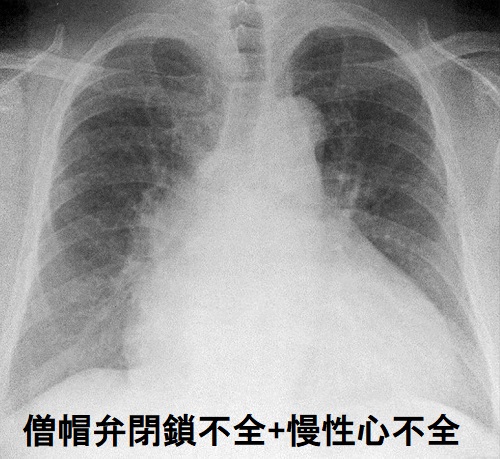

心臓弁膜症に甲状腺機能亢進症が合併すると心不全悪化・不整脈誘発。僧帽弁狭窄症による心房細動は甲状腺機能亢進症/バセドウ病誘発性と鑑別。甲状腺機能亢進症/バセドウ病の30%に僧帽弁逸脱症。バセドウ病、甲状腺機能低下症では僧帽弁の粘液水腫性変化で僧帽弁閉鎖不全症(MR)、僧帽弁腱索/乳頭筋断裂。甲状腺癌患者の大動脈弁狭窄症(AS)は人工心肺により癌細胞が全身に飛び散るため経カテーテル大動脈弁留置術(TAVI)適応。速脈は甲状腺機能亢進症や大動脈弁閉鎖不全症(AR)で出現。甲状腺機能亢進症/バセドウ病による高拍出量性右心不全で三尖弁閉鎖不全症。

心臓弁膜症による慢性心不全が基礎疾患として存在すると、甲状腺機能亢進症が加われば、

僧帽弁狭窄症(MS)では

- 肺うっ血;慢性肺疾患にかかり易い

- 右心不全;左心不全と異なり、進行が緩やかで症状が出にくく見逃される事が多い 疲れやすい、息切れがするなどの症状、頚静脈怒張、足のむくみ(下腿浮腫)を認める